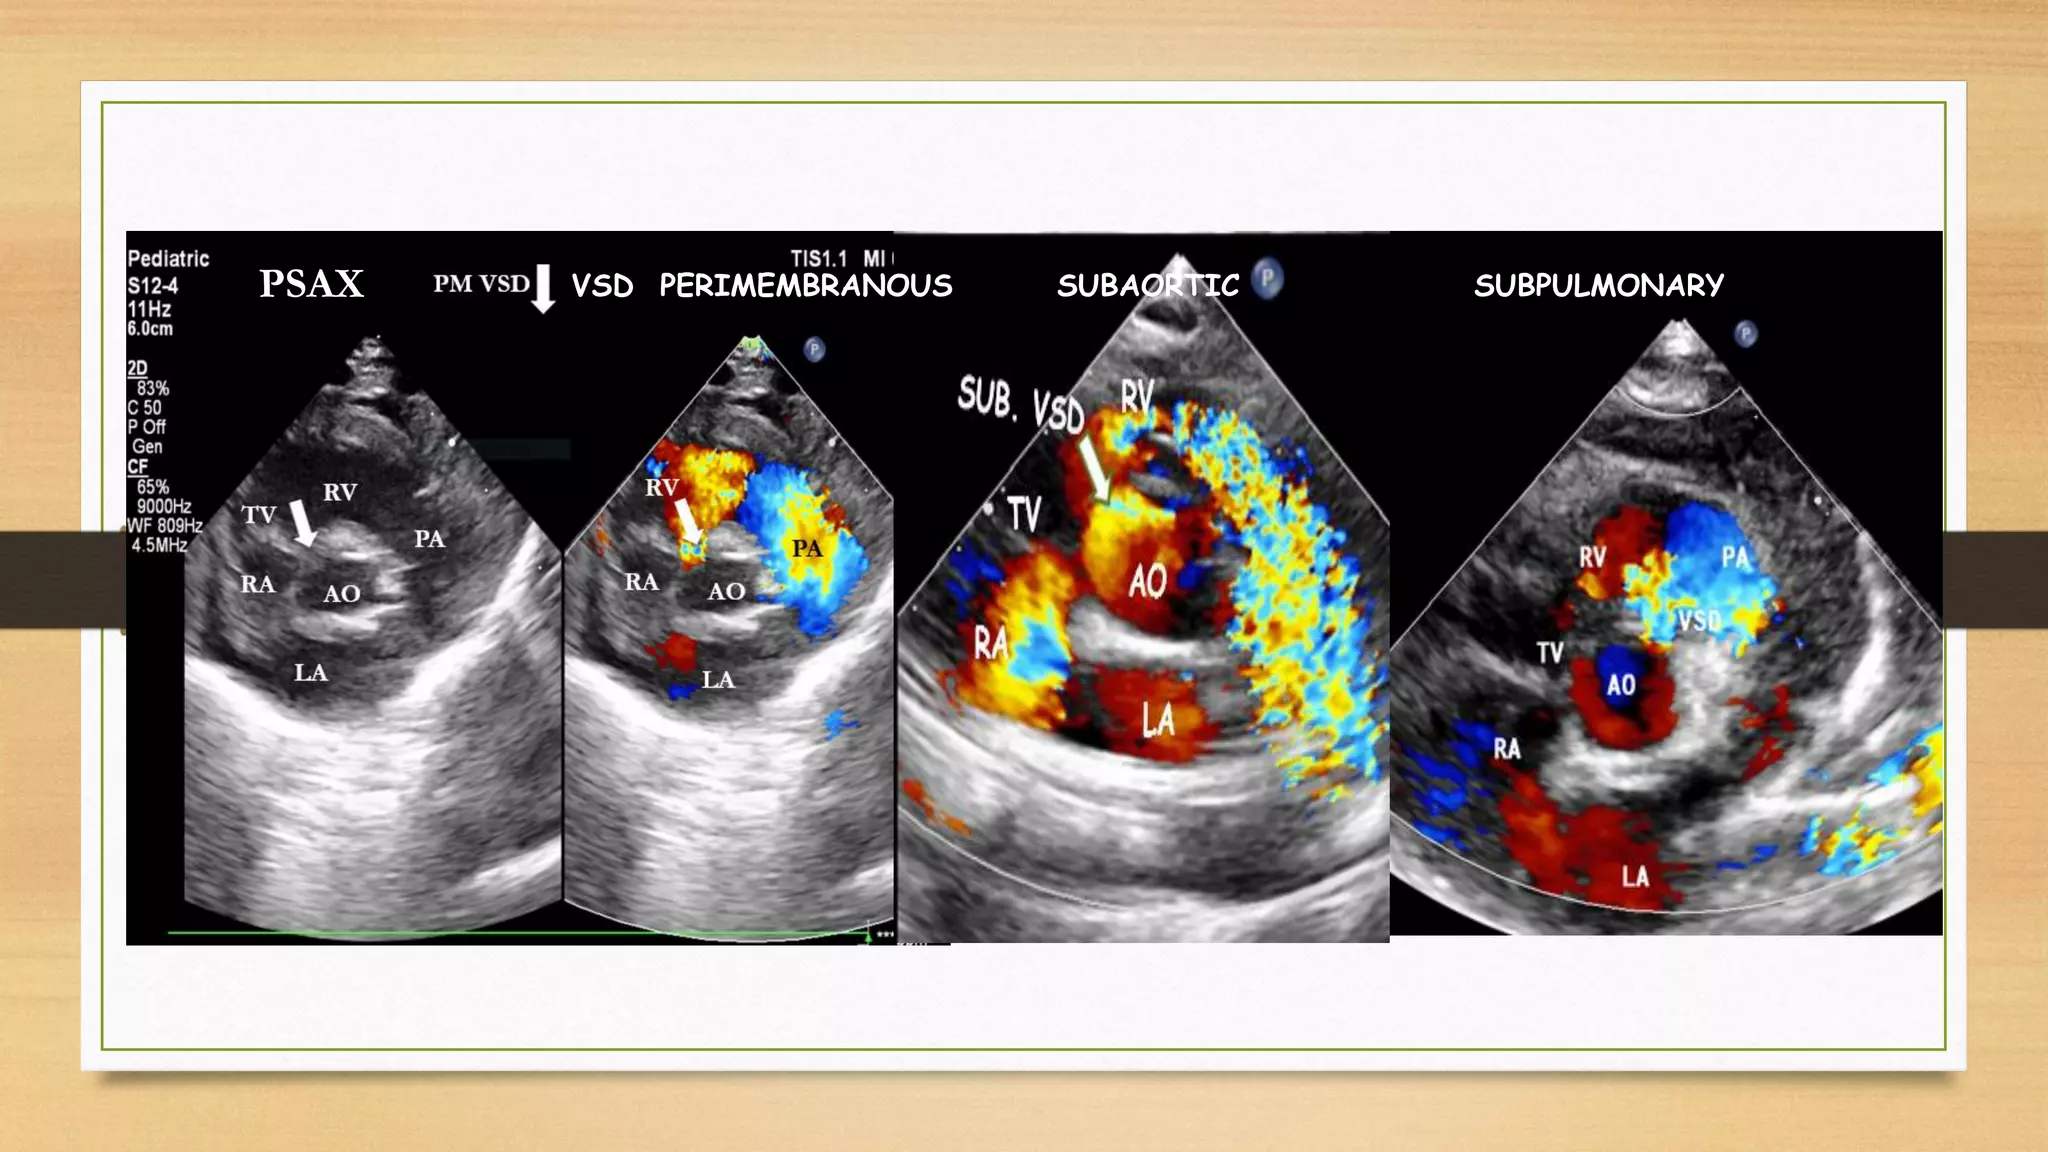

VSD PERIMEMBRANOUS SUBAORTIC SUBPULMONARY

PSAX

P L AX VIEW PERI MEMBRANOUS VSD SUB-AORTIC VSD SUB PUL. VSD - ECHO CARDIOGRAPHY : It is the essential tool for finding out size and location of V S D beside assessing size of heart, degree & direction of shunt for the management of patient.